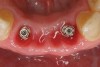

Figure 5  Tapered implants with conical transgingival abutments and temporary cylinders in place.

Figure 5

Preoperatively, 1 g of amoxicillin was administered. Using local anesthesia (lidocaine 1:100,000 epinephrine), extractions of teeth Nos. 23 to 26 were performed without raising a flap and with gentle luxation to preserve the remaining facial osseous plate. The sockets were curetted prior to implant placement. A vacuum-formed surgical guide, fabricated based on a diagnostic wax-up of the desired tooth positions for the subsequent fixed prosthesis, was used during implant placement. Osteotomies were performed at site Nos. 23 and 26 and positioned toward the lingual aspects of the sockets (Figure 3 and Figure 4). Two tapered implants (OsseoTite™ 313, BIOMET 3i™, www.biomet3i.com) measuring 3.25 mm x 13 mm were placed. Conical prosthetic abutments (3-mm height) were used to facilitate joining the two implants in a screw-retained FPD (Figure 5). A laboratory-processed acrylic-resin provisional restoration was altered to allow connection to the temporary cylinders. The provisional was placed into the vacuum-formed surgical guide that was now used to maintain the provisional in the correct 3-dimensional position (Figure 6) while being attached to the temporary cylinders with acrylic resin intraorally. Once a sufficient amount of acrylic resin was placed to secure the cylinders to the provisional, it was removed from the mouth and its contours were completed at the laboratory bench (Figure 7). The two central incisor sockets were grafted with small-particle allograft material (Puros® Allograft, Zimmer Dental, www.zimmer.com) to maintain the gingival architecture beneath the two ovate pontics (Figure 8). The provisional restoration was inserted and the screws were tightened to 20 Ncm of torque.